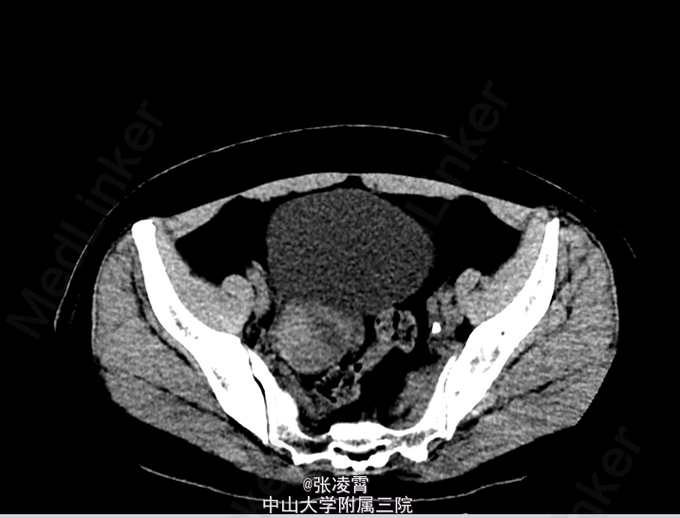

查体:双侧肾区叩击痛(+)。 血常规:白细胞 12.03 ×109 /L;中性粒百分比0.758 尿常规:白细胞 1647.3个/L;红细胞 1135.4个/L 大便常规,凝血四项,生化全套,术前八项等未见明异异常。 KUB示:右肾结石,左侧输尿管下段结石。 CT提示:右肾结石并右肾积水,左侧输尿管下段结石并输尿管扩张。 胸片,心电图大致正常。

诊断:1、左输尿管结石并左肾盂积水;2、右肾结石并积液。 入院第二天最高体温 39℃,目前予以舒普深 3.0 Bid 抗感染治疗三日后,体温正常,复查尿常规白细胞42个/L。予完善相关术前准备后行左侧输尿管镜下钬激光碎石取石术+右侧PCNL术。手术过程顺利。术中出血约30ml,耗时3h。